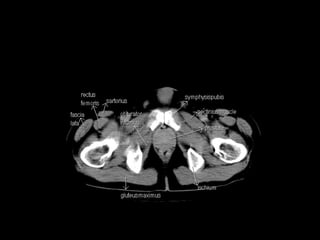

Radiographers use medical imaging equipment like X-rays and MRIs to produce images of patients' internal structures and organs. They are responsible for positioning patients, operating scanning machines, and ensuring quality images. Radiographers must have strong attention to detail, excellent communication skills, and the ability to work well under pressure to accurately capture anatomical features and diagnose any abnormalities.